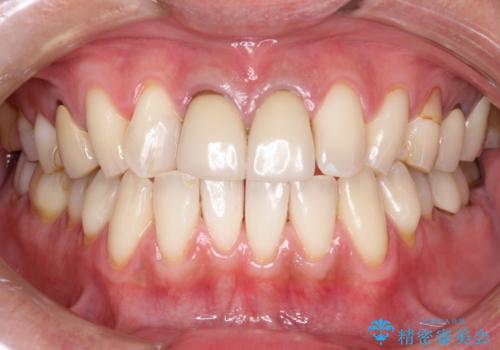

前歯の着色をPMTCできれいに

担当医 歯科衛生士